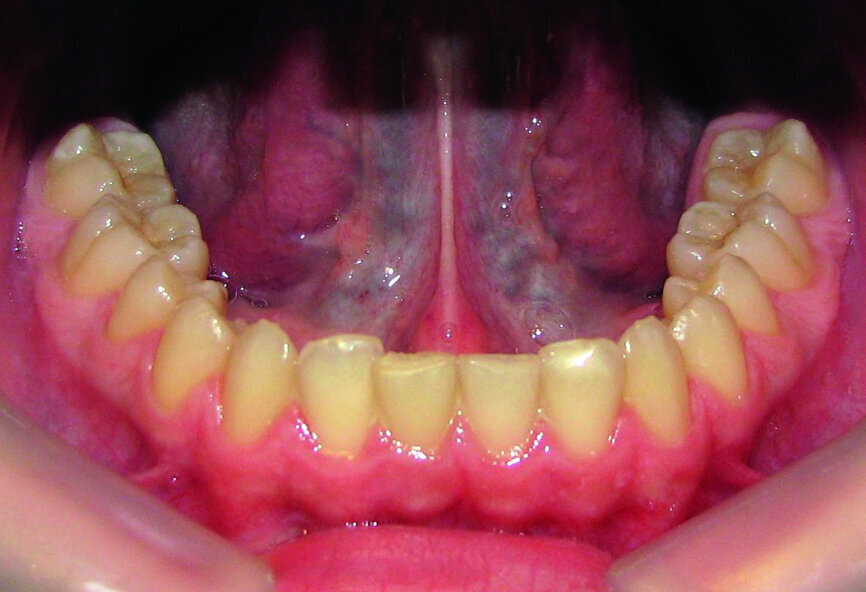

Then occlusal analysis (Figs. 11–21) was performed:

- Upper spacing due to the laterals agenesis (Fig. 18).